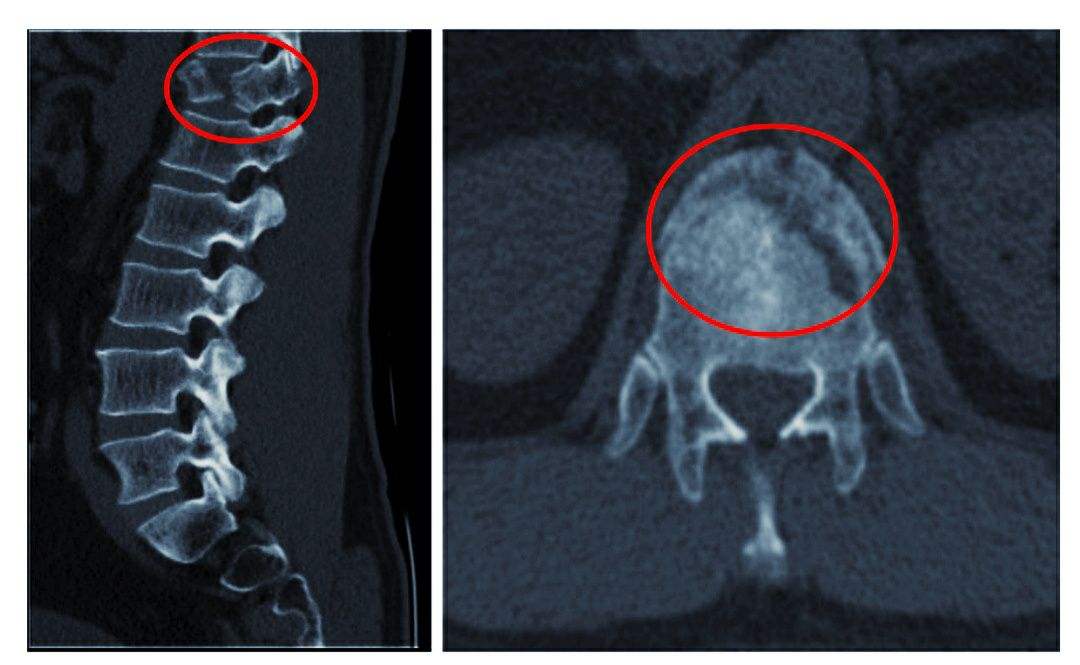

5、颈椎骨折

由于颈椎骨折,可造成出血,水肿,或碎骨片移位波及到椎间孔或椎管,直接压迫颈神经根或颈脊髓。骨痴的形成,使椎管、椎间孔发生狭窄性改变,产生脊髓、神经根的受压症状。